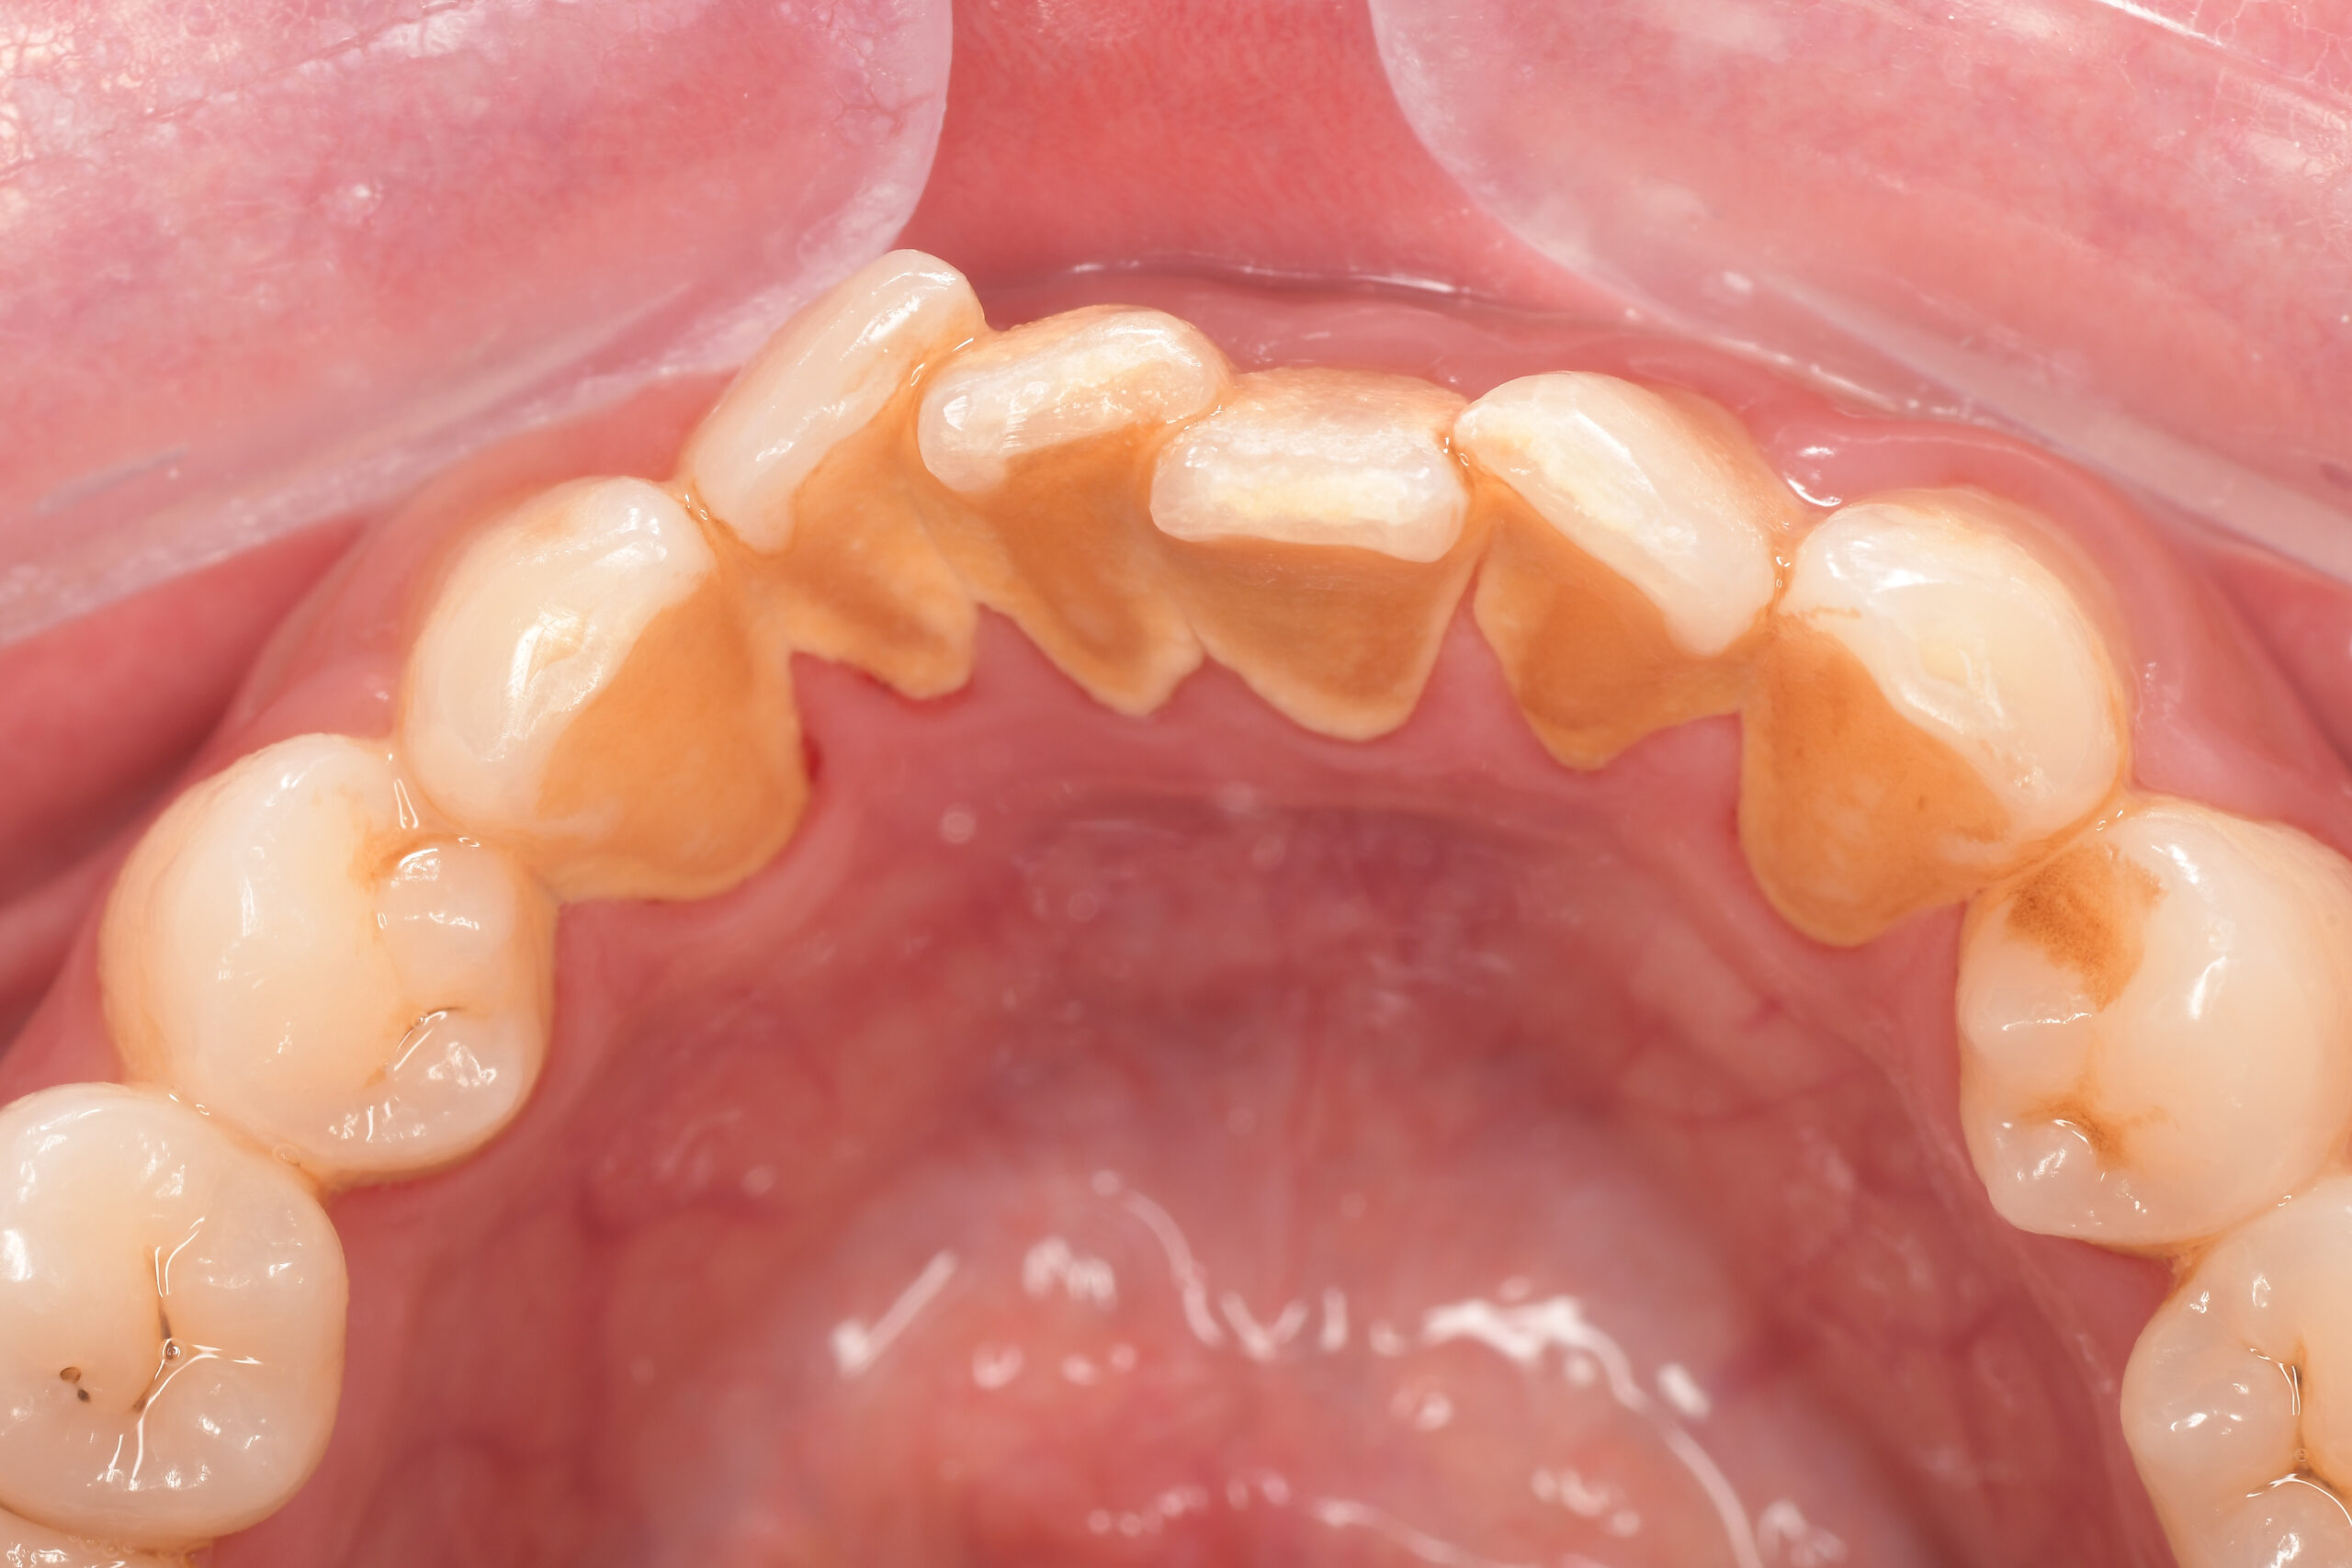

Before

After

基本情報

| 年齢・性別 | 52歳・女性 |

|---|---|

| 主訴 | クリーニングしたい |

| 治療内容 | スケーリング・PMTC |

| 治療期間 | 60分 |

| 治療費 | 約7,000円 |

| リスク・副作用 | 知覚過敏、歯肉退縮 |

| 治療方針 | 歯石とステインを除去して、今後は定期検診でのクリーニングと併せてガムピーリングやホワイトニングを行います。 |

| 担当者所見 | 歯肉の色素沈着が目立つため、ガムピーリングを行いながらホワイトニングを行うことをおすすめします。 |